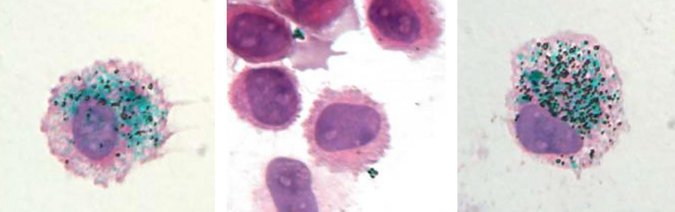

Cuando se da un tatuaje, los macrófagos descienden para capturar la tinta invasora. Probablemente porque los gránulos de tinta son demasiado voluminosos para que se descomponga el microscópico Pac-Mans. Se aferran al pigmento y el arte de su cuerpo brilla a través de sus vientres.

Luego, al observar las biopsias de tatuajes bajo el microscopio, los científicos vieron a los macrófagos cargados de glóbulos de tinta. Y la historia de los tatuajes se convirtió en uno de los sistemas inmunes. Aun así, se creía que los macrófagos que llevaban tatuajes eran estables y duraderos. Lo que les daba a los tatuajes su permanencia. Lo que sugiere este estudio es que, al menos en ratones, estos macrófagos se reemplazan constantemente.

Al tatuar rayas verdes en las colas de ratones albinos (a través de stick-and-poke), los inmunólogos confirmaron que los macrófagos secuestraban la tinta. Cuando mataron selectivamente a los macrófagos, los tatuajes de la cola se mantuvieron sin cambios; nuevos macrófagos habían entrado y sorbían los pigmentos liberados.